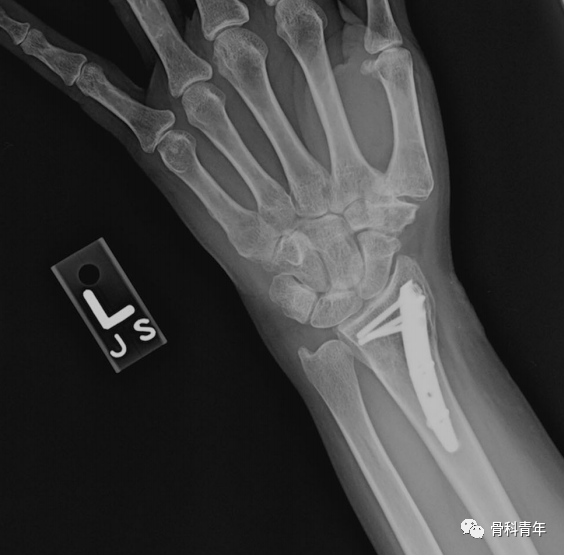

一、桡骨远端髓内钉

髓内钉技术广泛应用于长骨骨干骨折,闭合或有限切开复位有效降低医源性因素对血运的破坏,并具有良好的轴心固定生物学优势。桡骨远端髓内钉出现较晚,该技术适用于完全关节外骨折及简单的关节内骨折,对关节内粉碎骨折并不适用

桡骨远端骨折髓内钉固定的前提是闭合复位效果满意,克氏针临时固定后,通过桡骨茎突开口,自腕背侧第1/2间室间隙进入。该技术存在潜在的损伤包括桡神经分支损伤,螺钉穿入下尺桡关节或桡腕关节等。